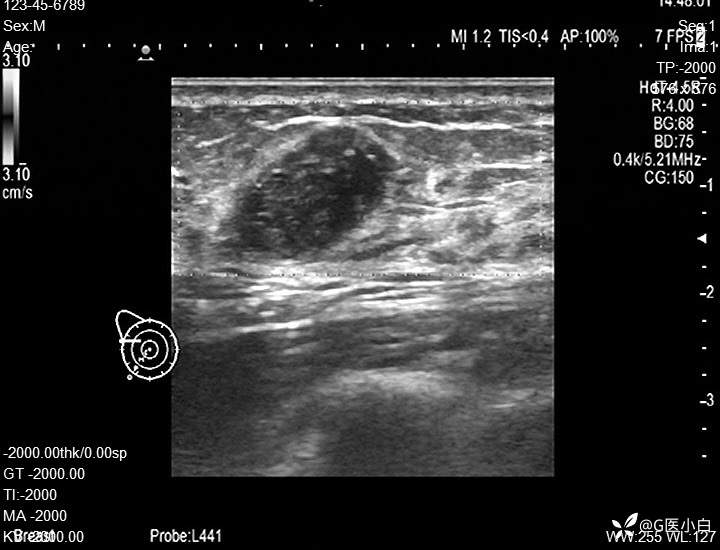

病例阅乳大师•彩超篇41|发现右乳肿物2月余

患者性别:女748737

患者年龄:43岁

主诉:发现右乳肿物半年余